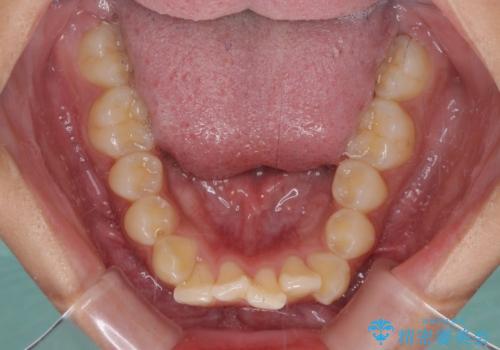

- 下唇に上顎前歯の跡がつくくらいに突出した前歯とデコボコを気にして来院された患者様です。

口元の突出感改善のため、上下左右の第一小臼歯4本を抜歯し、ワイヤー装置にて矯正治療を行うこととしました。

それほど口元の突出感が強いわけではありませんでしたが、下唇に前歯引っかかる感触が気になっていたため、抜歯矯正を行うこととしました。

上下前歯の被蓋が理想通りに改善され、患者様には大変満足していただけました。